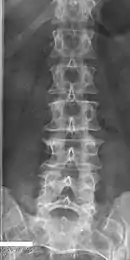

Butterfly vertebrae

Butterfly vertebrae have a sagittal cleft through the body of the vertebrae and a funnel shape at the ends. This gives the appearance of a butterfly on an x-ray. It is caused by persistence of the notochord (which usually only remains as the center of the intervertebral disc) during vertebrae formation. There are usually no symptoms. There are also coronal clefts mainly in skeletal dysplasias such as chondrodysplasia punctata. In dogs, butterfly vertebrae occur most often in Bulldogs, Pugs, and Boston Terriers.[9]

Butterfly vertebra (red). Normal vertebra for comparison (blue).

Volume rendering of a CT scan of the lumbar vertebral column, showing butterfly vertebrae at several levels, most typically in L1.